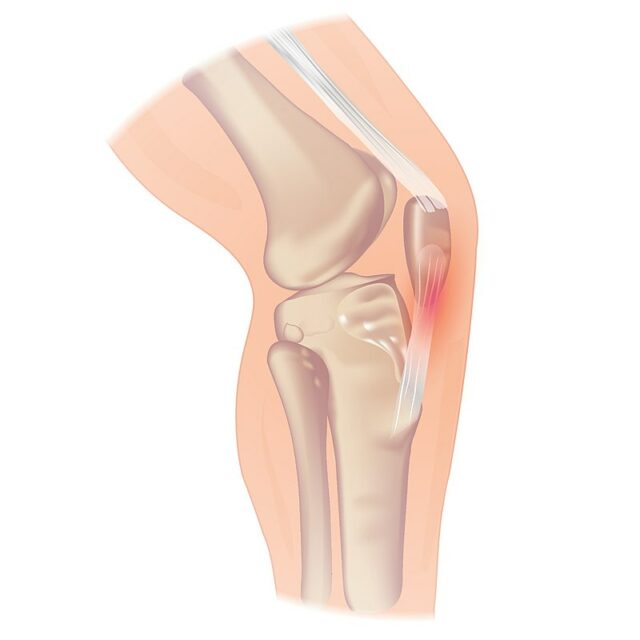

La tendinopatia rotulea può verificarsi al polo inferiore della rotula, ma anche all'inserzione del tendine sulla tuberosità tibiale, più raramente. Se un paziente riferisce un dolore alla base della rotula, si può sospettare una tendinopatia del quadricipite.

Si noti che l'irritazione del cuscinetto adiposo di solito si presenta con un dolore più diffuso ed è solitamente aggravata da una sovraestensione del ginocchio. Nei giovani atleti all'inizio della pubertà, le patologie della placca di crescita devono essere tenute presenti: La più comune è la malattia di Osgood-Schlatter, una lesione da uso eccessivo caratterizzata dall'ossificazione dell'osso lungo il piatto di crescita in corrispondenza del tubercolo tibiale. Nella versione più grave, la Osgood Schlatter può comportare un piatto di crescita della tuberosità tibiale non fuso. La Sinding Larsen Johannson è l'equivalente della Osgood Schlatter, solo che ora è interessato l'apice della rotula.